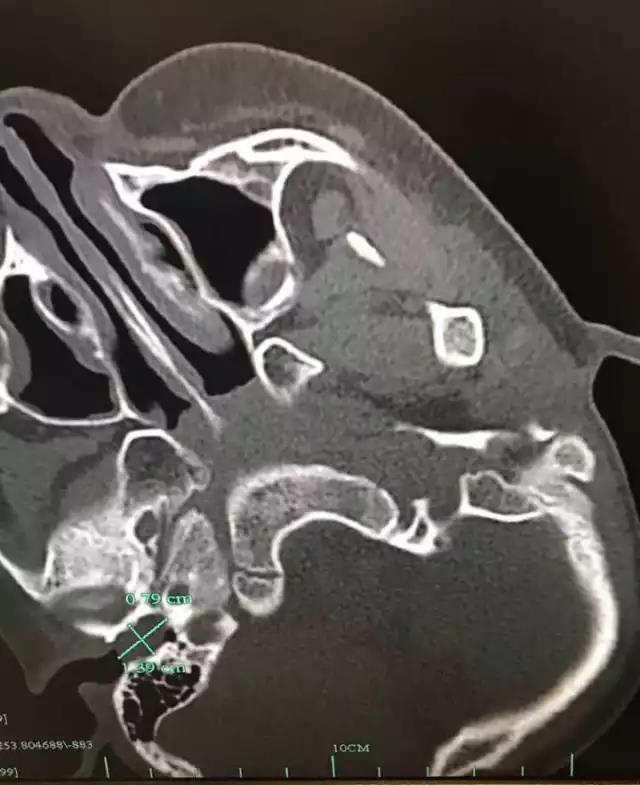

一块长约1.4公分,宽约0.8公分的耳屎堵在耳朵里是怎样一种感觉?如果这个耳屎还硬... |